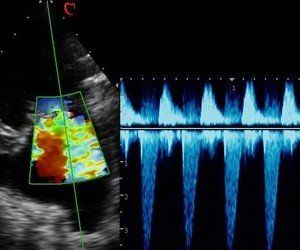

Échographie

Cardiaque

Notre appareil d'échographie est équipé d'une sonde phased d'array, d'un doppler et d'un électrocardiogramme qui nous permettent d'explorer le fonctionnement du coeur, de dépister et de suivre certaines affections cardiaques.